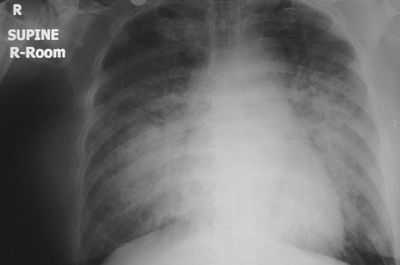

Также обязательным является проведение электрокардиограммы. На ЭКГ отмечаются признаки перегрузки правого желудочка, нарушения ритма сердца или признаки ишемии и некроза миокарда при остром инфаркте. Сама по себе ЭКГ не покажет отек легких, но она поможет выявить причину кардиогенного отека легких, а в результате правильного лечения эта причина будет устранена. Кроме ЭКГ, экстренно выполняется рентгенография легких, которая помогает установить диагноз.

Диагностика хронической сердечной недостаточности

Диагноз ХСН врач может установить исходя из жалоб и осмотра больного. Для подтверждения диагноза используются ЭКГ, УЗИ сердца и рентгенография легких. На кардиограмме отмечаются признаки перегрузки правого желудочка, постоянная форма мерцательной аритмии, изменение электрической оси сердца (ЭОС), постинфарктного кардиосклероза или постинфарктной аневризмы ЛЖ. Рентгенограмма выявляет венозное полнокровие в легких, а при тяжелых стадиях - гидроторакс (скопление жидкости в плевральной полости, иногда требующей хирургической пункции).

изменения на рентгеновском снимке при левожелудочковой недостаточности